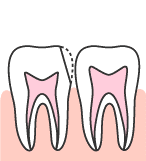

虫歯がエナメル質を超えて、その下の象牙質にまで及ぶと、病変は急速に広がって行きます。

象牙質はエナメル質と違って、それほど硬くないためです。

そのため、表面では小さな穴でしか無くても、奥ではとても大きなものになっている場合が多いのです。